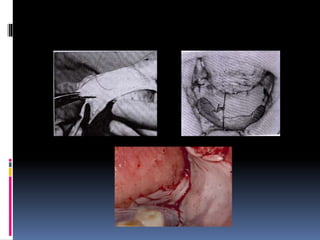

13. Stent for vestibuloplasty and skin graft

ridge during healing period after sulcus deepening

 Protect and immobilize the graft, prevent hematoma formation,, help the graft to takes

Construction:

 Modification of the ridge and sulcus depth is made on the cast ,modified cast is waxed, flasked and

processed into clear acrylic resin. graft placed on the stent with its raw surface facing upward

 The stent may be lined with the soft liner, may be wired to the ridge (circumferential wiring)